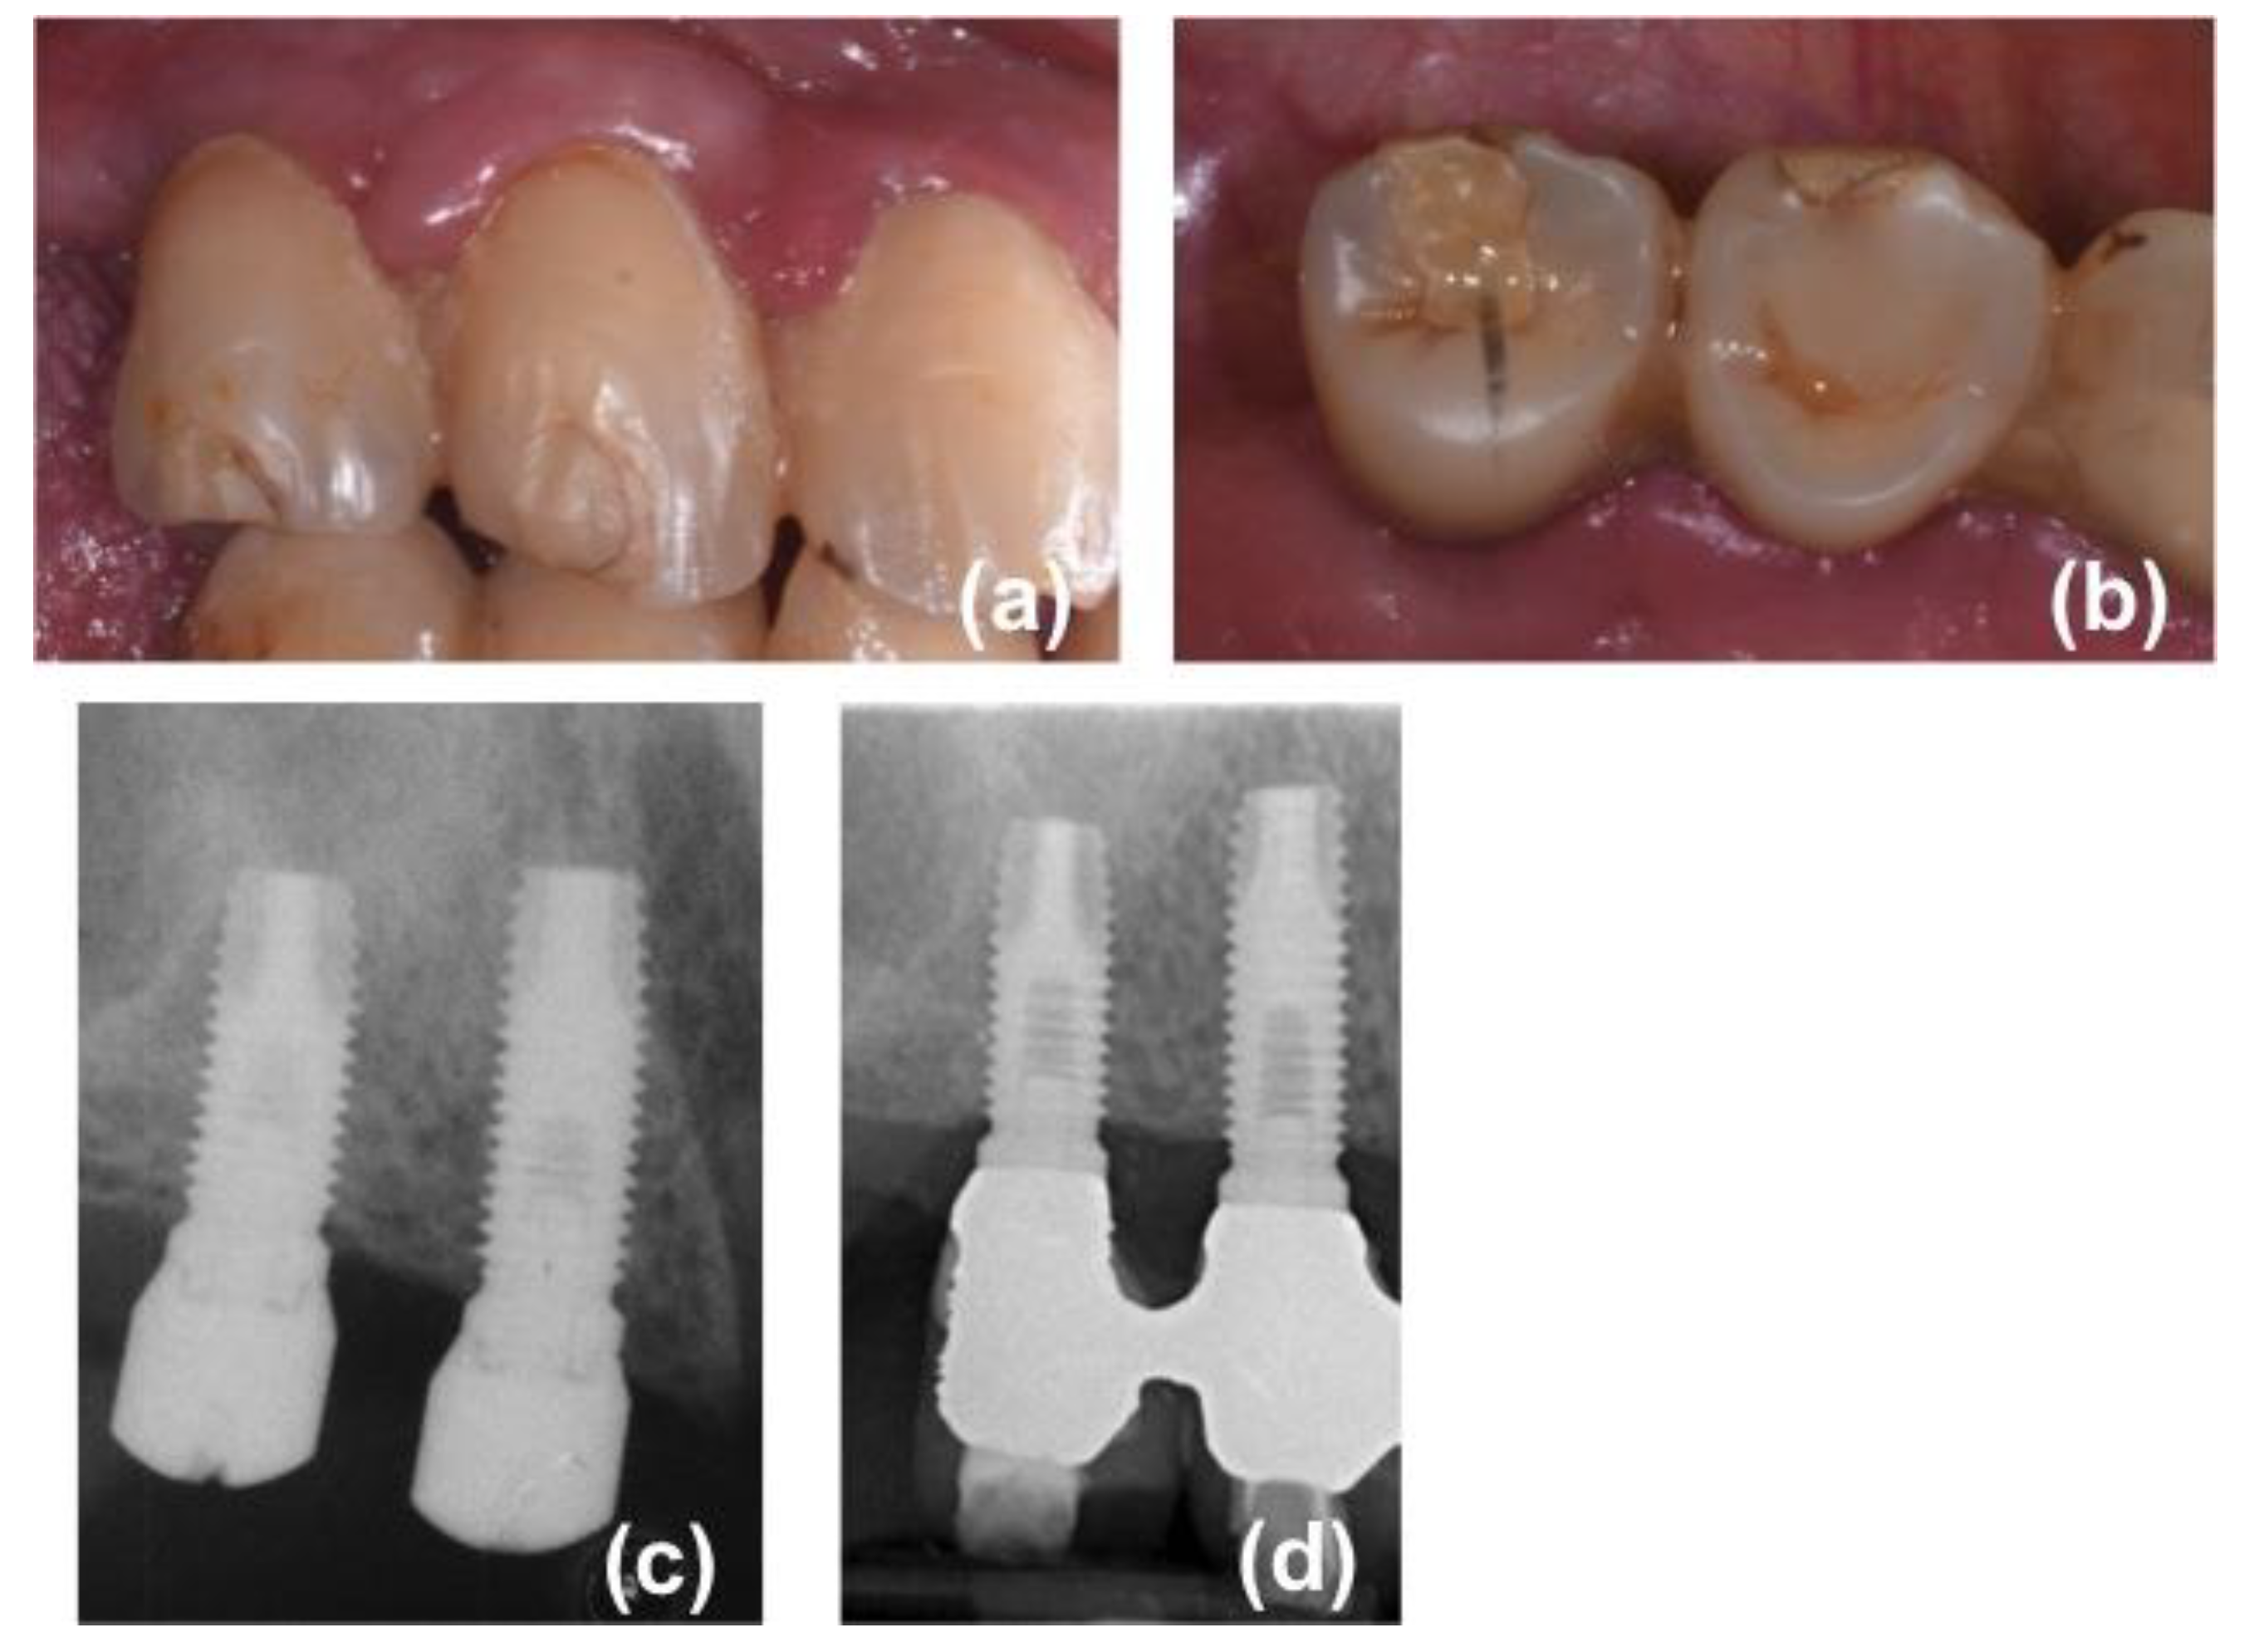

Screw-retained prostheses, provided with a metal framework and composite resin veneering material, were delivered 5–6 months (mean 24 weeks) after surgery (Figure 1).

Figure 1. One of the patients included in the present research: (a) intraoral view of the bridge at the five-year follow-up appointment; (b) occlusal view of the bridge at the five-year follow-up appointment; (c) endoral radiograph three months after implant insertion; (d) endoral radiograph taken at the five-year follow-up appointment.